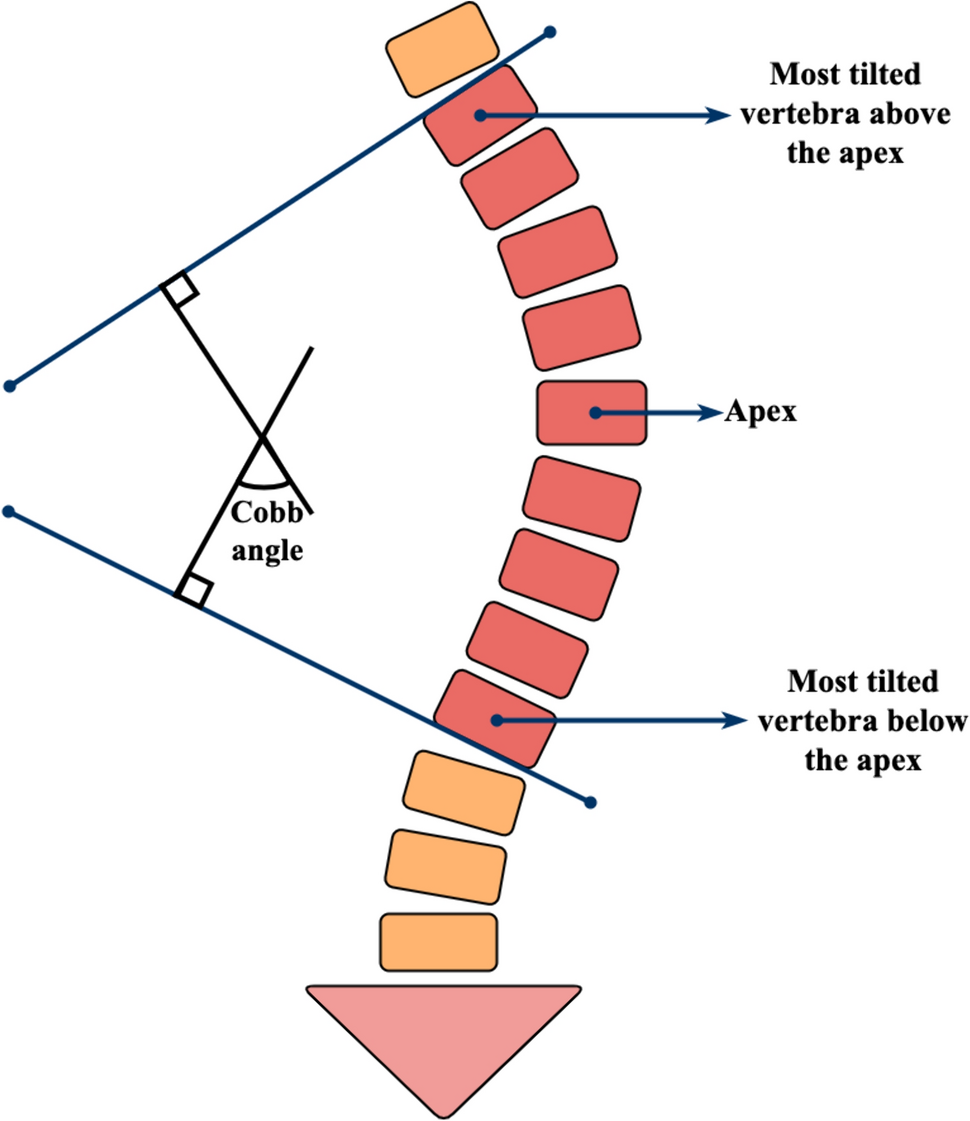

ثانيًا: أهمية قياس زاوية كوب (Cobb Angle)

تُعتبر زاوية كوب هي الطريقة العالمية الأساسية لقياس درجة اعوجاج العمود الفقري.

📌 كلما زادت الزاوية، زادت شدة الحالة.

قياس زاوية كوب

👉 بشكل مبسط:

- 10 إلى 24 درجة: اعوجاج بسيط

- 25 إلى 49 درجة: اعوجاج متوسط

- 50 درجة فأكثر: اعوجاج شديد

ومن المهم أن نفهم أن هذه الزاوية ليست رقمًا فقط، بل تساعد الطبيب على تحديد خطة العلاج المناسبة بدقة. لذلك، فإنها عنصر أساسي في متابعة الحالة.